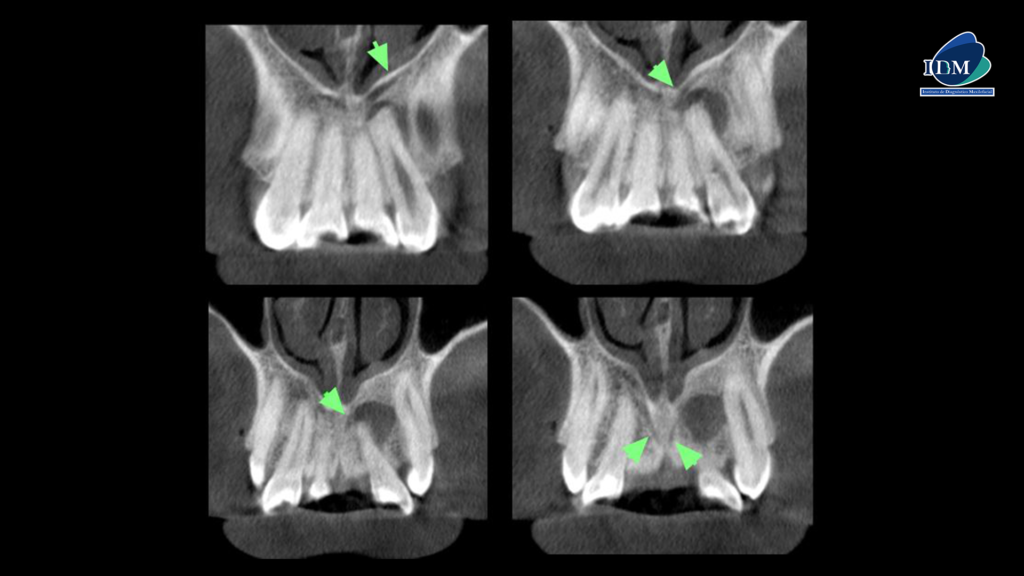

A la evaluación de los cortes transaxiales y tangenciales se observa la discreta invaginación de la pieza 22 (flecha naranja), así como el recorrido del canalisis sinuosus (flecha verde) y la presencia de la lesión osteolítico próxima a este.

En la reconstrucción 3D se observa de manera más gráfica y además se confirma la presencia de un canal accesorio que nace del canal sinuoso del lado derecho.

CORTES TANGENCIALES